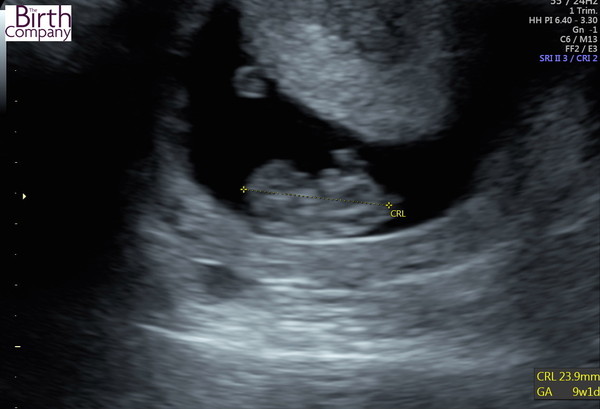

The early scan went well Grin measuring about right for the dates (9+1 according to LMP) with a strong heartbeat. Am so relieved, had really convinced myself there would be a problem.

That's great news feeling. Lovely scan picture Grin